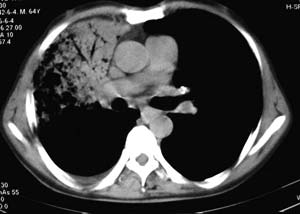

右侧胸廓略小于左侧,右肺上叶大片实变影,近肺门处密度较高,内见支气管气相,周围较淡,呈网格状,余肺野清晰,纵隔内见肿大淋巴结,右侧胸腔少量积液。临床 咳血,咳痰 发热 , 血象1.2万。

考虑大叶性肺炎。

影像表现:肺窗示右肺上中叶均可见小片、条索状、小结状密度增高影,可见支气管充气相,小叶间隔增厚,支气管通畅,余肺未见明显异常。纵隔窗示4r可见小淋巴结融合,无明显肿大,右侧示少量胸腔积液。

右侧胸阔塌陷,纵隔右移。右上肺大片状高密度影,沿支气管血管束走行,内见点状钙化;支气管充气征阳性,支气管呈柱状扩张;胸膜下小叶间隔增厚;右侧后胸壁内侧见带状水样密度影;纵隔淋巴结增大。

考虑:①右上叶陈旧性结核合并感染可能大。②右侧少量胸水。